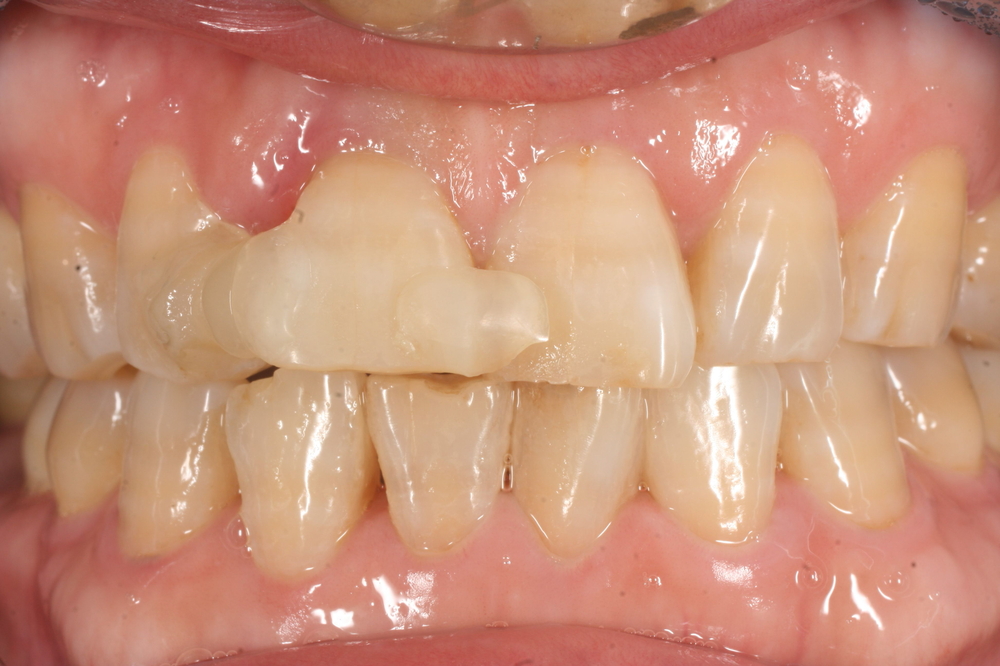

このように歯が割れている場合、まずは歯を保護するための応急処置を行います。

隣の歯と接着剤で一時的に固定し、痛みやぐらつきを抑えた状態で精密検査を進めました。

CT撮影を行うと、割れ目が歯根の深い部分まで達していることが分かりました。

このようなケースでは、差し歯(クラウン)などの保存的治療では改善が難しく、

抜歯を前提とした治療計画が必要になります。